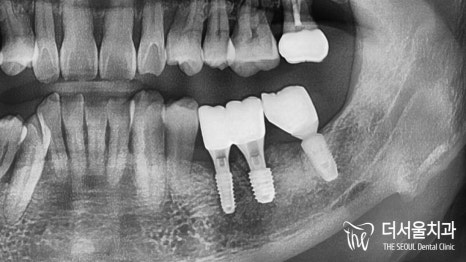

미리 결정된 식립 위치에 맞춰

컴퓨터분석임플란트 식립을 마무리 했습니다.

오늘도 해내는 더서울.. (짝짝짝)

가지런하게, 그리고 예쁘게 심어드렸습니다.

emergency profile도 딱 알맞게 형성되어 있는 모습이네요.

오래오래 보철을 사용하실 수 있도록

주의사항 및 관리법을 다시 한 번 강조드렸습니다.